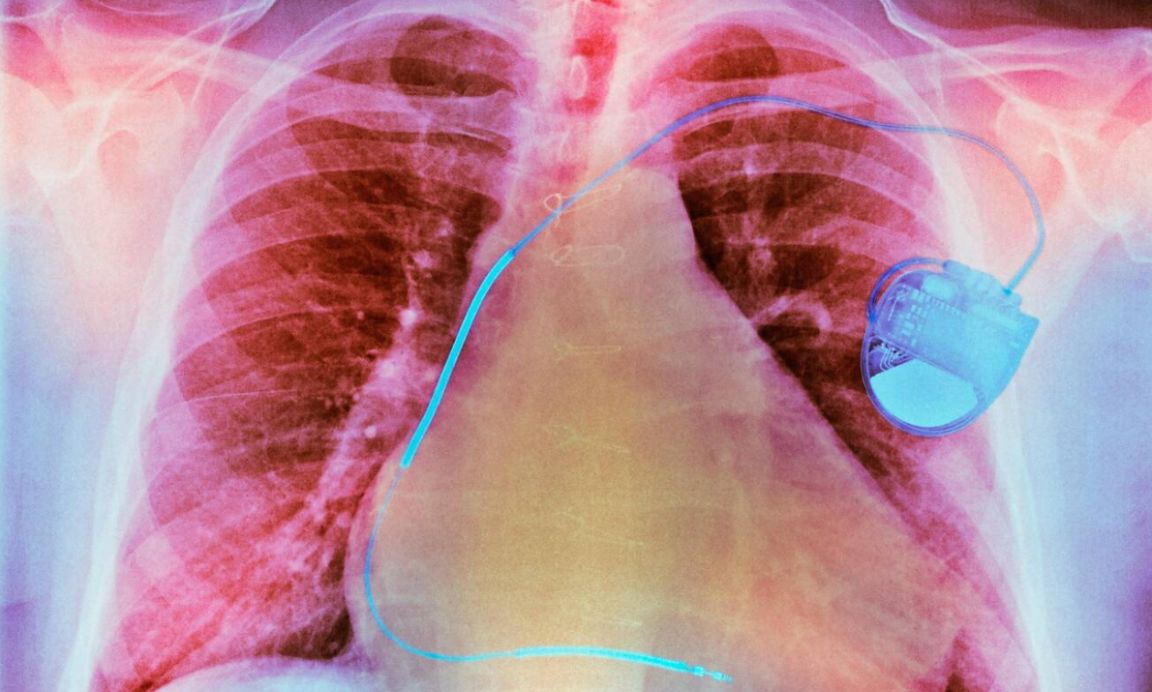

Medical technology is responding to this growing burden of chronic disease with digital tools that monitor vital signals like blood glucose levels. Modern med-tech is culminating in what Professor Muireann Quigley, Professor of Law, Medicine and Technology at the University of Birmingham, calls integrated goods – devices so intimately connected to our bodies that they blur the line between human and machine, transforming us into 'everyday cyborgs'.

They include conventional devices like pacemakers and artificial limbs and emerging applications, from smart-e-pants that deliver electrical stimulation to prevent bed sores to biosensitive tattoo ink that change colour when athletes become dehydrated. Such gadgets interact with the human body dynamically, generating troves of intimate, personal data with implications for legal questions like identity, autonomy and control.

“Medical devices like pacemakers are unequivocally pieces of property when they're manufactured or sold to the NHS, but whose property are they once implanted into or attached to patients – the NHS’s or the patient’s?” Professor Quigley asks. “Answers to this are not clear because there is a hybridity here – of person and thing – that the law doesn’t yet adequately take account of and confounds our traditional legal categorisations. We have to start conceptualising these things in a different way because it’s not just about the device or the person.”

Questions of rights and control are deeper than data, however. Traditional property law insists that only things separate from persons can be property. But a pacemaker isn't separate – it's under the skin, functioning from the inside. “In some cases, without this medical device, there would be no subject, because it is helping keep the person alive,” Professor Quigley notes, “but overall, this challenges the very doctrinal foundations of law.” The distinction between person and property, fundamental to centuries of legal thinking, begins to dissolve.

If the pacemaker malfunctions, is this a property law issue or personal injury? If you modify your insulin pump's software, are you tampering with someone else's intellectual property or exercising control over your own body? These questions can determine who bears liability when things go wrong, who can authorise repairs, and ultimately who controls life-sustaining technology.